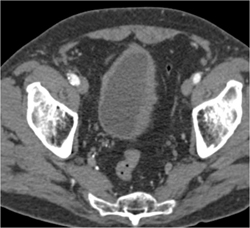

Bladder Cancer